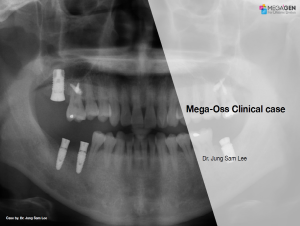

Aesthetic zone,AnyRidge,Clinical case,Dr. Achraf Souayah,Edentulous,Guided surgery,Immediate Placement,Mandibular Anterior,Mandibular Posterior,Maxillary Anterior,Maxillary Posterior,MEG-Rhein,MILA Kit,Overdenture system,Sinus Elevation